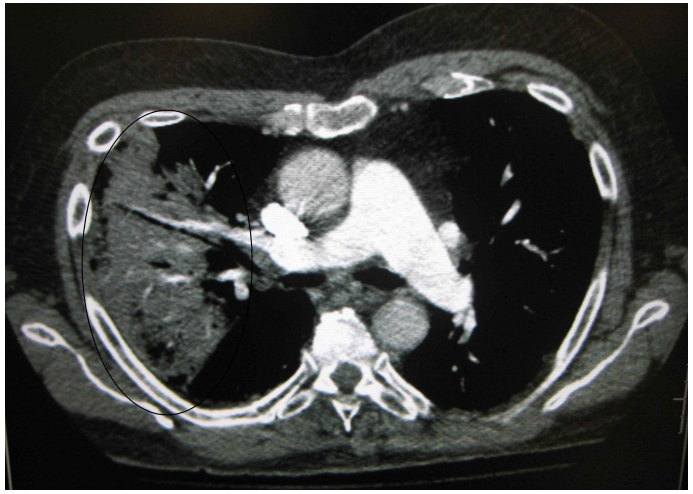

2) Chest CT

흉부 전산화 촬영(computed tomography, CT) 검사는 폐실질 이상 소견을 평가하는 데 있어서 가장 정확한 검사로, 흉부 X선 검사에서 이상소견이 없는 경우에도 폐렴에 합당한 영상 소견을 보일 수 있다. 또한, 늑막염 및 폐실질 괴사와 같은 폐렴 합병증의 진단, 무기폐, 폐경색, 종양, 간질성 폐질환 등과 같이 폐렴과 유사한 X선 소견을 보일 수 있는 다양한 비감염성 폐질환의 배제 및 감별진단에 있어서 흉부 X선 보다 더욱 정확하다.

또한 CT에서 나타나는 여러 소견들이 폐렴의 원인균에 따라 차이를 보일 수 있어서 원인균을 추정하는 데에도 유용할 수 있으며, 일반적인 폐렴과 반드시 감별해야 하는 Mycobacteria, 진균에 의한 감염성 폐 질환 등을 추정할 수 있는 소견을 보일 수 있다.

다만 흉부 X선 검사에 비해서 높은 가격과 방사선 조사에 따른 위험성 등을 감안했을 때, 폐렴 환자에서 CT 검사는 폐색전증 등 다른 동반 가능한 질환에 대해 감별이 필요한 경우, 진균성 감염이 의심되는 경우, 다른 기저 폐질환 등으로 인해서 흉부 X선에서 폐 침윤 여부를 확인하기 어려운 경우, 폐렴 치료에 잘 반응하지 않아서 폐렴의 합병증을 확인하기 위한 경우 등 특수한 상황에서 선택적으로 시행이 고려될 수 있다.